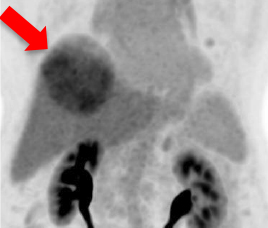

- 治疗前Tc MAA SPECT/ CT

- 预测肿瘤与非肿瘤钇90粒子分布

- 识别分流至肺部及内脏

- 钇90选择性内部放射治疗

- 使用鍀99m MAA(左)模拟钇90粒子分布(右)

- 评估治疗可行性

- 由双示踪剂正电子/电脑双融扫描计算处方剂量

- 用正电子/电脑双融扫描显示钇90粒子分布(右)

99mTc MAA SPECT/CT Y-90 PET/CT